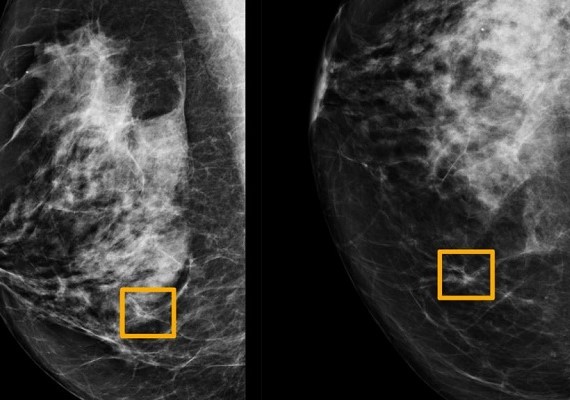

Google AI System Could Improve Breast Cancer Detection

An artificial intelligence system found cancer